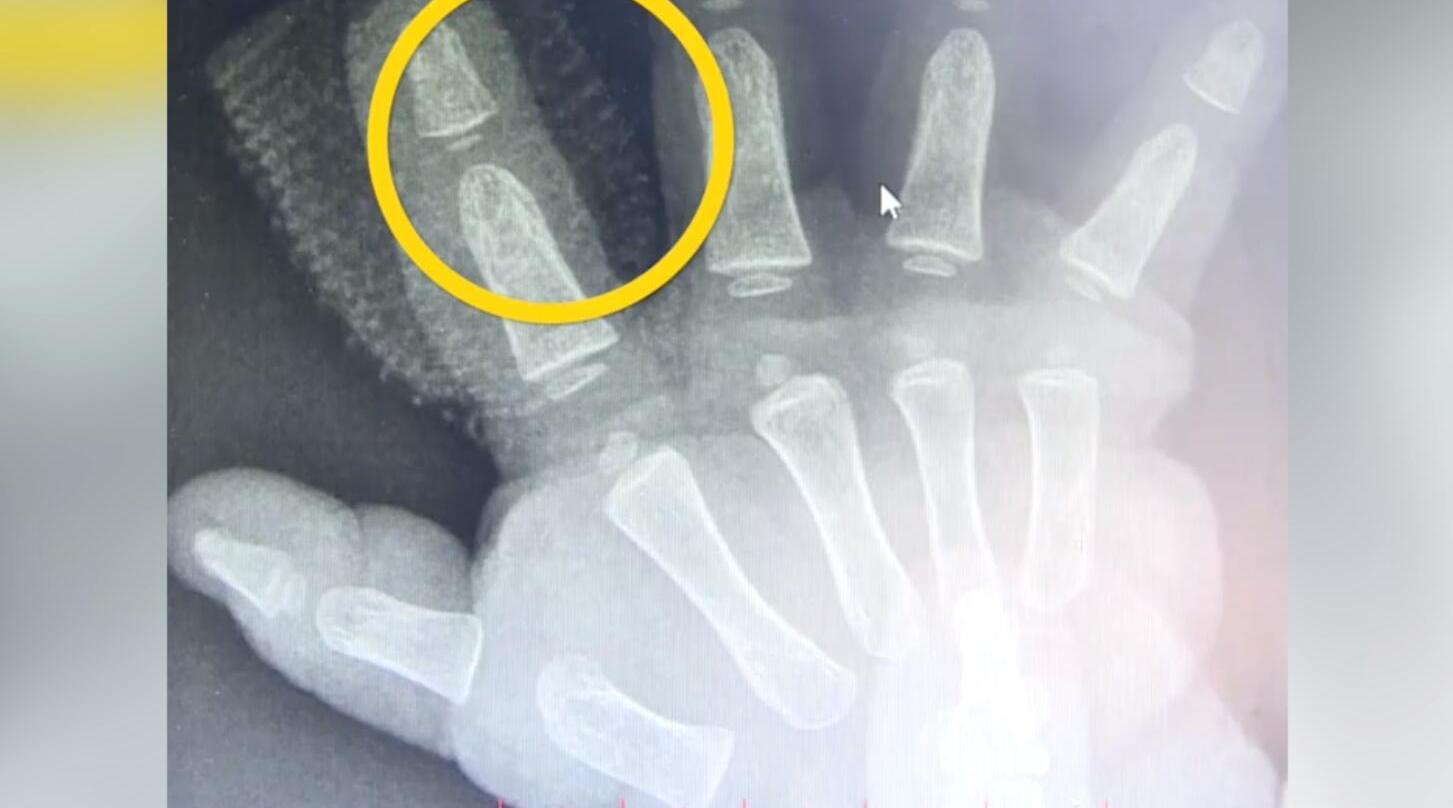

近日,在陕西宝鸡发生了一件让人痛心的事情,一名1岁多的女童被家里养的兔子咬掉了一根食指的指尖。当时,小女孩正在家里和兔子玩耍,突然就被咬了,食指的末节一个指头盖完全掉了,家长赶紧送孩子去医院。

可是由于当地医院治疗条件有限,家长最后又花了6个小时赶到宝鸡高新医院求医。医生给小女孩实施了断指再植手术,目前小女孩的恢复情况良好。

如果被兔子咬断了手指,第一时间肯定是先把手指给抢回来,兔子咬断的这个手指,跟其他的一些手指断的情况还要好一些,因为它是锋利,所以它的断面非常的整齐,这样在接的时候比其他的那种撕断的、铡断的什么的,成功率要多得多。如果找不回来,那孩子很可能就终生顶着一双有缺陷的手了。